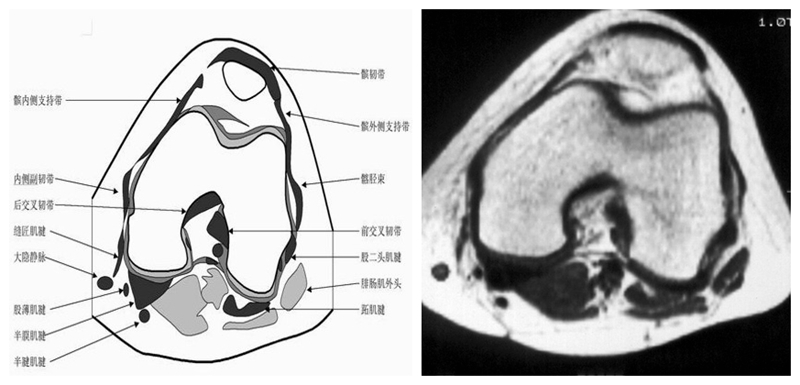

膝关节横断面MRI解剖

三维影像首选的方位,便于与CT比较,可准确地展现髌骨内外侧关节面。

横断面解剖第三层